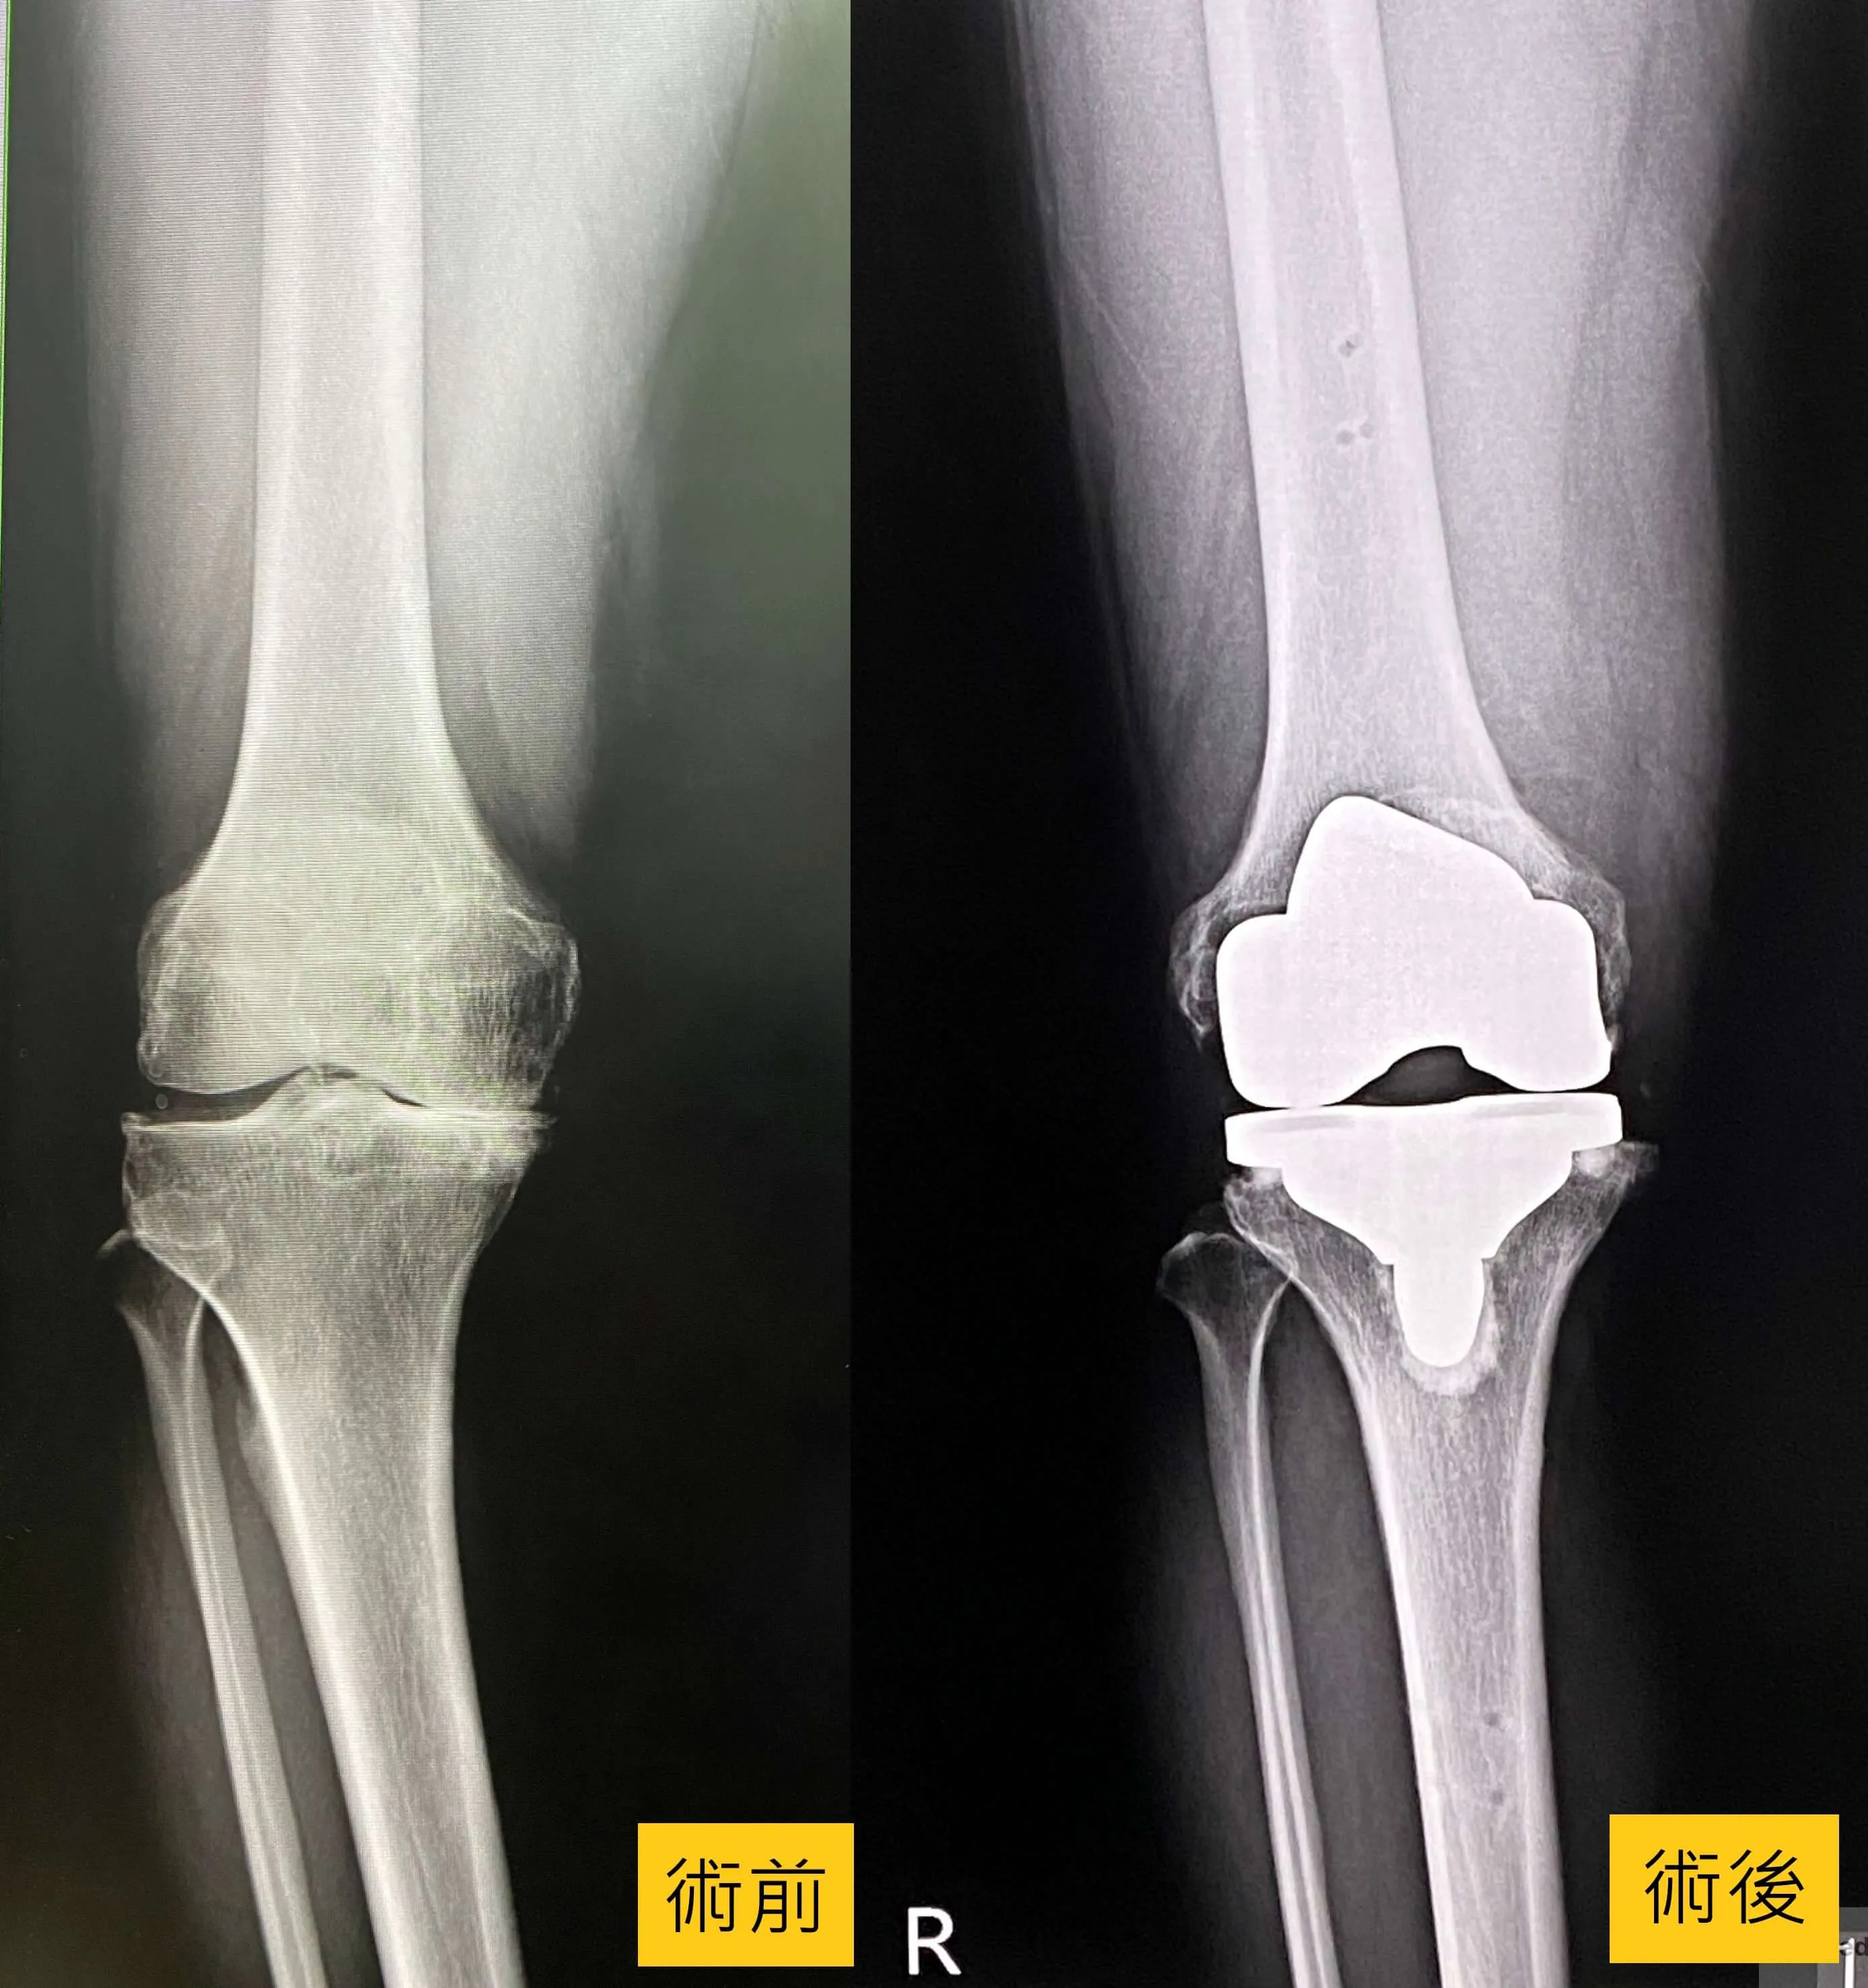

骨科主任楊志鴻醫師表示,透過X光檢查可以發現歐先生的腳已經有O型腿現象,是因為過去的膝蓋舊傷造成關節不穩定,加速軟骨的磨損,退化性關節炎非常嚴重,必需置換人工關節。經過進一步的探討,了解精準置換手術效果及人工關節使用的年限後,最終歐先生選擇接受「MAKO機器手臂人工關節置換術」。